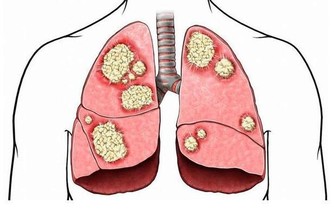

氣毒氣毒是存在肺裡面的毒,中醫認為“肺主氣”、“腎主納氣”,有氣毒的人往往肺腎功能不好,一般身上氣味大,如有口臭、汗臭等。為了防止氣毒,可以每天早起做深呼吸,即“呼吸吐納”,把肺中的濁氣排出來,保持體內空氣的新鮮。